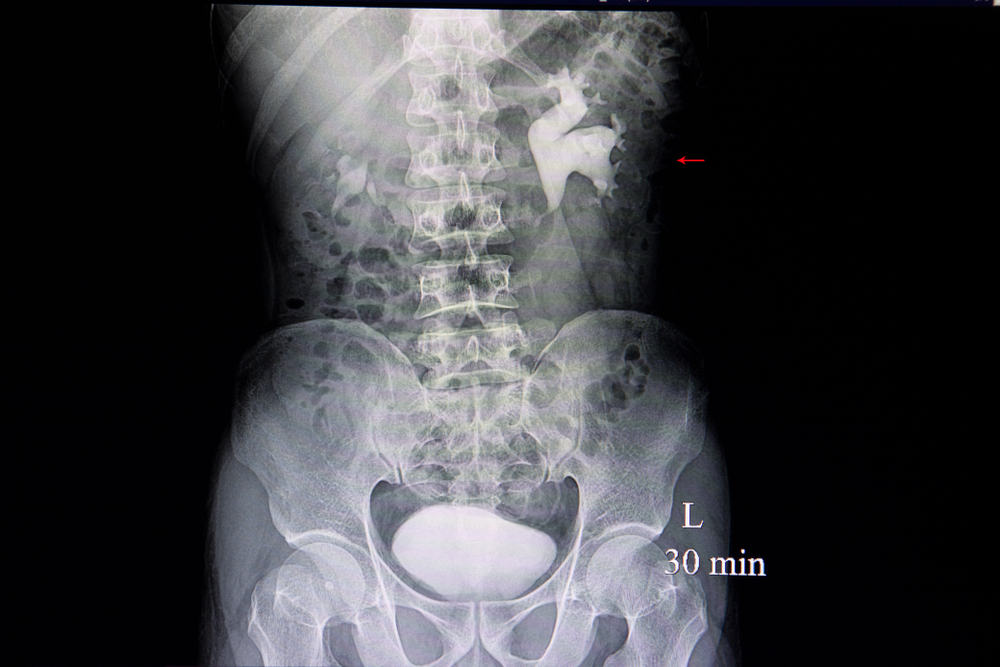

इंट्रावेनस पायलोग्राम टेस्ट (IVP) को अंतःशिरा मूत्रमार्ग भी कहा जाता है। यह एक रेडियोलॉजिकल प्रक्रिया होती है जिसका उपयोग गुर्दे, मूत्रवाहिनी और मूत्राशय सहित मूत्र प्रणाली की असामान्यताओं की जांच करने के लिए किया जा सकता है। इसमें गुर्दे, मूत्रवाहिनी और मूत्राशय के एक्स-रे को देखने के लिए नसों के जरिए शरीर में आयोडीन युक्त विपरीत सामग्री का इस्तेमाल किया जाता है। साथ ही, इनका इस्तेमाल शरीर के दूसरे हिस्से के लिए भी किया जा सकता है। इंट्रावेनस पायलोग्राम टेस्ट में एक्स-रे और डाई का इस्तेमाल करके आपकी किडनी और यूरेटर ट्रैक्ट को दिखाया जाता है। यह आपकी किडनी, ब्लैडर और यूरेटर की फोटो खींचता है। यूरेटर एक ट्यूब है जो यूरिन को किडनी से ब्लैडर में ले जाता है। यदि आपको यूरिनरी ट्रैक्ट या पेट में दर्द की समस्या है तो आपका डॉक्टर इंट्रावेनस पायलोग्राम टेस्ट के लिए कह सकता है। IVP डॉक्टर के क्लिनिक या अस्पताल में किया जा सकता है।

इंट्रावेनस पायलोग्राम के लिए परीक्षण टेबल पर पीठ के बल लेटना होता है। एक्स-रे मशीन आमतौर पर टेबल के एक हिस्से से जुड़ी होती है। इमेज इंटेन्सिफायर- मशीन का वह हिस्सा जो छवियों को प्राप्त करता है, आपके पेट के ऊपर रखा जाता है। जब आप परीक्षण टेबल पर सहज हो जाते हैं, तो प्रक्रिया आगे बढ़ाई जाती है।

IVP खत्म होने के बाद, एक्स-रे इमेज आने में लगने वाला समय सभी लैब में अलग-अलग होता है। इमेज आने के बाद रेडियोलॉजिस्ट इसकी समीक्षा करता है। आपके डॉक्टर को इसकी एक प्रति भेजी जाती है। आमतौर पर परिणाम आने में 1 या 2 दिन का समय लगता है। डॉक्टर परिणाम के बारे में आपसे चर्चा करने के बाद आगे के उपचार के बारे में बताएगा।